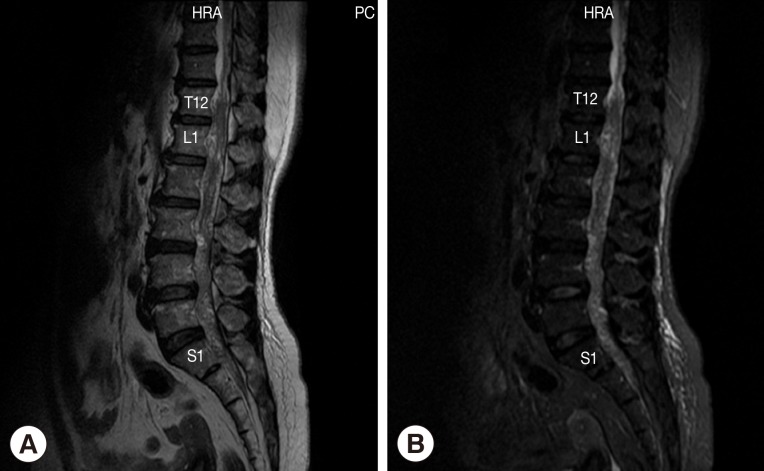

Fig. 1

Magnetic resonance of lumbosacral spine sagittal T2W image (A) and sagittal T2W with fat suppression image (B) shows abnormal lower lumbar spinal cord, conus medullaris, and cauda equina. Multiple heterogeneously serpigineous lesion filling within T12 to S1 of the thecal sac.

The patient was a 52-year-old female sugarcane farmer who lived in a rural community of Suphan Buri Province, central Thailand. She presented to our hospital complaining of lumbodorsal pain for the previous month, progressive symmetrical paraparesis with sensory impairment and radiculopathy for 2 weeks, and bowel/bladder dysfunction for 3 days. She had no history of ingesting inadequately cooked frogs, snakes, or birds. On examination, the patient had a normal body temperature. Skin nodules or organomegaly was not observed. Mental status and cranial nerve functions were within normal limits. Neurological examinations revealed decreased motor tone of both legs. Motor strength of the left lower extremity decreased from grade V (normal) to grade III in the hamstrings, iliopsoas, and quadriceps muscles; grade I-II in the ankle and toe plantar flexor muscles; and grade 0 in the ankle dorsiflexors muscles and the extensor hallucis longus muscle. For the right lower extremity, motor strength was decreased to grade III in all the muscles. Sensations were decreased below the L2 dermatome on both sides with peri-anal anesthesia, and the knee and ankle jerk were absent on both sides. Anal sphincter tone was reduced. A clinical diagnosis of cauda equina syndrome was made. Routine biochemical and hematological investigations were within normal limits except for an increase of absolute eosinophil count in the peripheral blood (0.46×109/L). MRI of the whole spine showed multiple intradural extramedullary serpiginous-mass lesions in the subarachnoid space continuously from the prepontine to the anterior part of the medulla oblongata levels, C7, T2-T8, and T12 vertebral levels distally until the end of the thecal sac, and filling-in of the right S1 neural foramen (Fig. 1). Attempts of spinal tapping to obtain a cerebrospinal fluid (CSF) sample were unsuccessful.

Fig. 1 Magnetic resonance of lumbosacral spine sagittal T2W image (A) and sagittal T2W with fat suppression image (B) shows abnormal lower lumbar spinal cord, conus medullaris, and cauda equina. Multiple heterogeneously serpigineous lesion filling within T12 to S1 of the thecal sac.